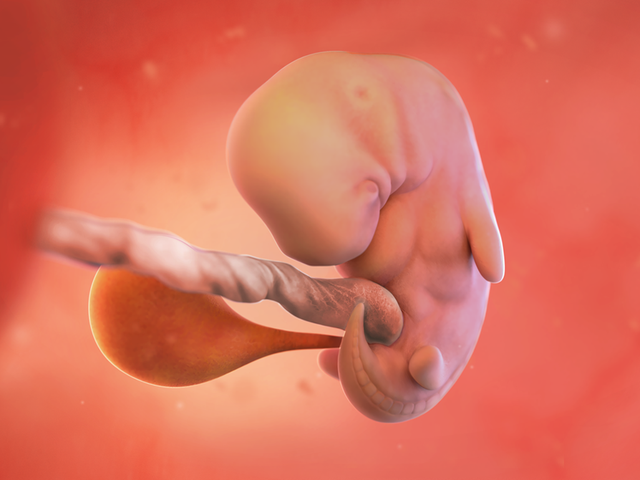

Bé yêu

– Bé yêu hiện là một phôi thai, dài khoảng 5-9mm (như hạt đậu), với tim đập đều đặn (110-160 lần/phút) – một khoảnh khắc đầy cảm xúc!

– Túi ối và nhau thai phát triển, cung cấp oxy và dưỡng chất cho bé.

– Đầu, mắt, tai, miệng, và chi sơ khai đang định hình, với cánh tay/chân như chồi nhỏ. Siêu âm có thể cho mẹ thấy túi ối, tim thai, và chi sơ khai. Thật tuyệt vời!